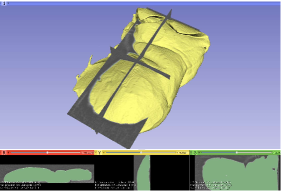

In order to evaluate the quantified accuracy of our 3D reconstruction method, we used the CT imaging of tissues as the gold standard. In this experiment, CT scans of four ex-vivo porcine livers and three kidneys were obtained (Siemens Somatom, Erlangen Germany) with a 0.6 mm resolution at our hospital, and we used the 3D Slicer software to segment the tissue models from the CT images, as shown in Fig. 9. We captured stereo videos of the tissues with the KARL-STORZ stereo laparoscope, the details of which are in Tab. II. Surfaces of livers and kidneys are very smooth and have low textures, but the proposed method was still able to reconstruct the 3D models, as shown in Fig. 7. To quantify accuracy, we registered the 3D reconstructed model with the CT segmentation results by first manually selecting landmarks, such as tissue tips, edge points and other recognizable points, and then refining the registration with the ICP algorithm. As shown in Fig. 7 (a), the root mean square errors (RMSE) with the liver cases are 1.3, 1.1, 1.4 and 2.0 mm respectively. The fourth liver case has a relatively larger error because we used an entire piece of liver and the video was captured at a larger camera-tissue distance. The results on porcine kidneys are shown in Fig. 7 (b), the RMSE of which are 1.0, 1.0 and 1.1 mm respectively. The histograms of errors are also provided in Fig. 7, which show that most points have an error of less than 2mm. It is worth noting that there are multiple sources of errors, including 3D reconstruction error, CT resolution error, CT segmentation error and registration error that contribute to the obtained RMSE in this experiment. In addition, because the livers and kidneys were placed on a textureless plastic sheet and part of the sheet were also included in the 3D reconstructed model, which is difficult to be totally removed (see the tissue edges in the distance maps of Fig. 7), so the quantified error may also include a small amount of the background. Therefore, it is a reasonable assumption that the actual error of our 3D reconstruction method is smaller than the reported RMSE.